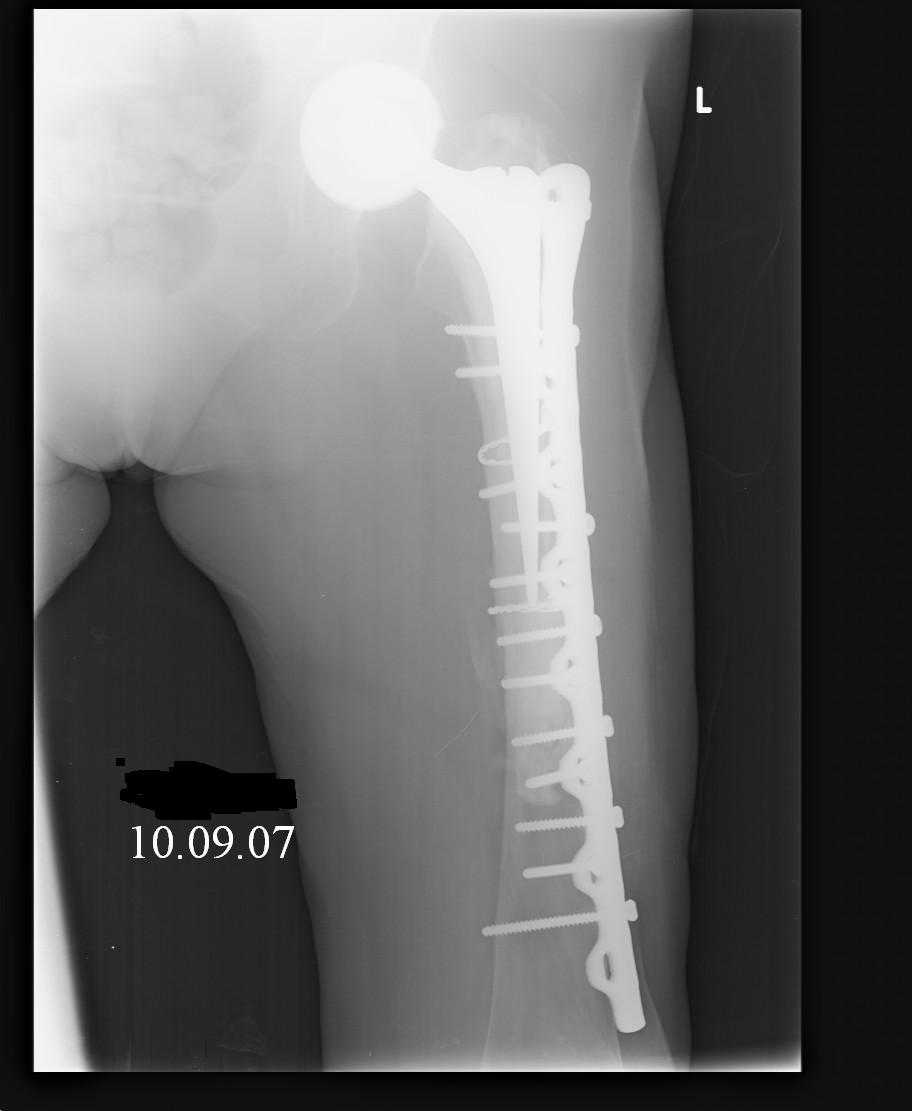

Re: Перипротезный перелом

Hello! This is just illustration in one of the choice of treatment